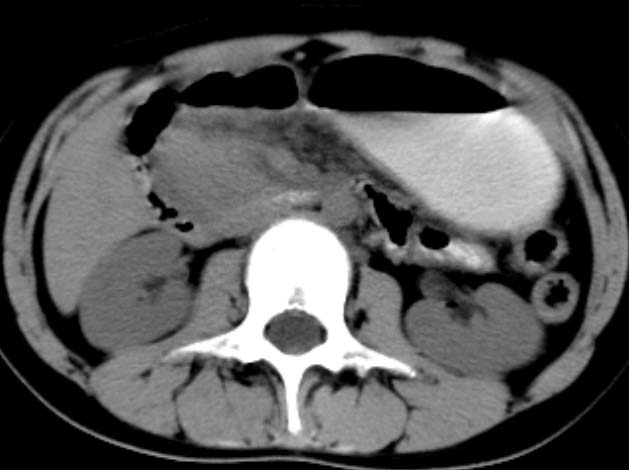

女,14岁。腹痛3天。腹部触诊未触及包块。碘剂阳性未增强。求助战友。。。。。。。。。。。

胰头部明显肿大,胰周间隙浸润,考虑胰腺炎可能性大

胰头部增大,周围模糊,有渗出,胰腺炎可能性大,建议结合化验检查;左侧输尿管上段略扩张.

胰头部明显肿大,胰头周脂肪密度加大。十二指肠环扩大受压。胰管未见确切扩张。考虑胰腺炎可能性大。建议增强扫描。

胰头部增大,周围结构模糊,并明显见渗出。支持:急性胰腺炎!

1)急性胰腺炎。2)肝右叶后上段肝内胆管结石。3)左侧输尿管上段扩张,原因待查。